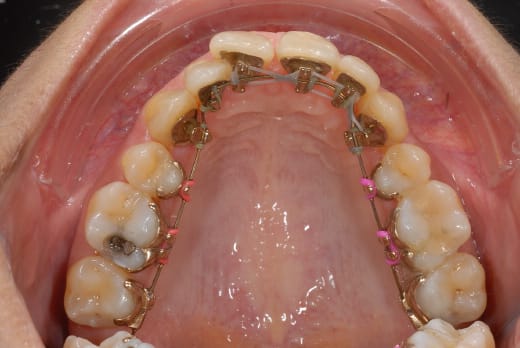

ben voilà des news en photo...

(et que personne me sape le moral...)

00184904 vui1ji - Eugenol

00184919 s85o5f - Eugenol

00184924 r1np2u - Eugenol

Apparemment, ton arc est du twist flex , souple et non traumatisant. Tu vas le garder un bon moment!!!!

Sois patiente, ma doc, ca va tres bien fonctionner.